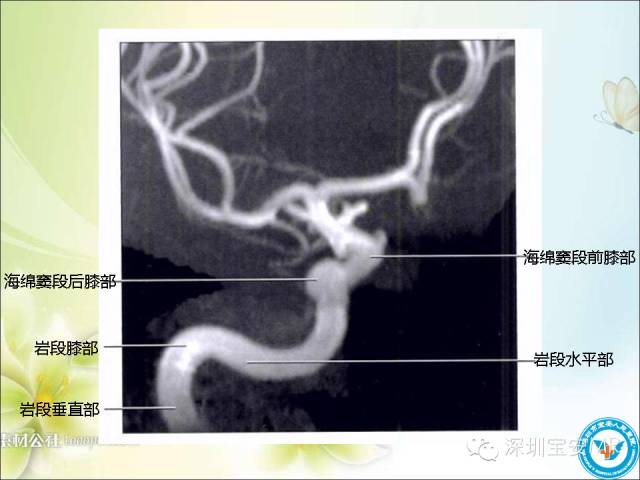

看了这么多,先来一段血管TOF的原始图像视频,对于了解颅内动脉走形及3D很有帮助的!